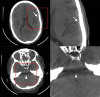

Photon-counting detector (PCD) CT is an emerging technology that has shown tremendous progress in the last decade. Various types of PCD CT systems have been developed to investigate the benefits of this technology, which include reduced electronic noise, increased contrast-to-noise ratio with iodinated contrast material and radiation dose efficiency, reduced beam-hardening and metal artifacts, extremely high spatial resolution (33 line pairs per centimeter), simultaneous multienergy data acquisition, and the ability to image with and differentiate among multiple CT contrast agents. PCD technology is described and compared with conventional CT detector technology. With the use of a whole-body research PCD CT system as an example, PCD technology and its use for in vivo high-spatial-resolution multienergy CT imaging is discussed. The potential clinical applications, diagnostic benefits, and challenges associated with this technology are then discussed, and examples with phantom, animal, and patient studies are provided. ©RSNA, 2019.